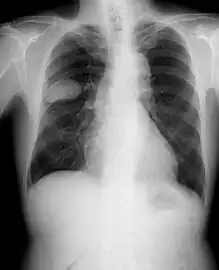

Frontal chest X-ray showing a probable S2–S3 small cell carcinoma in the right side lung.